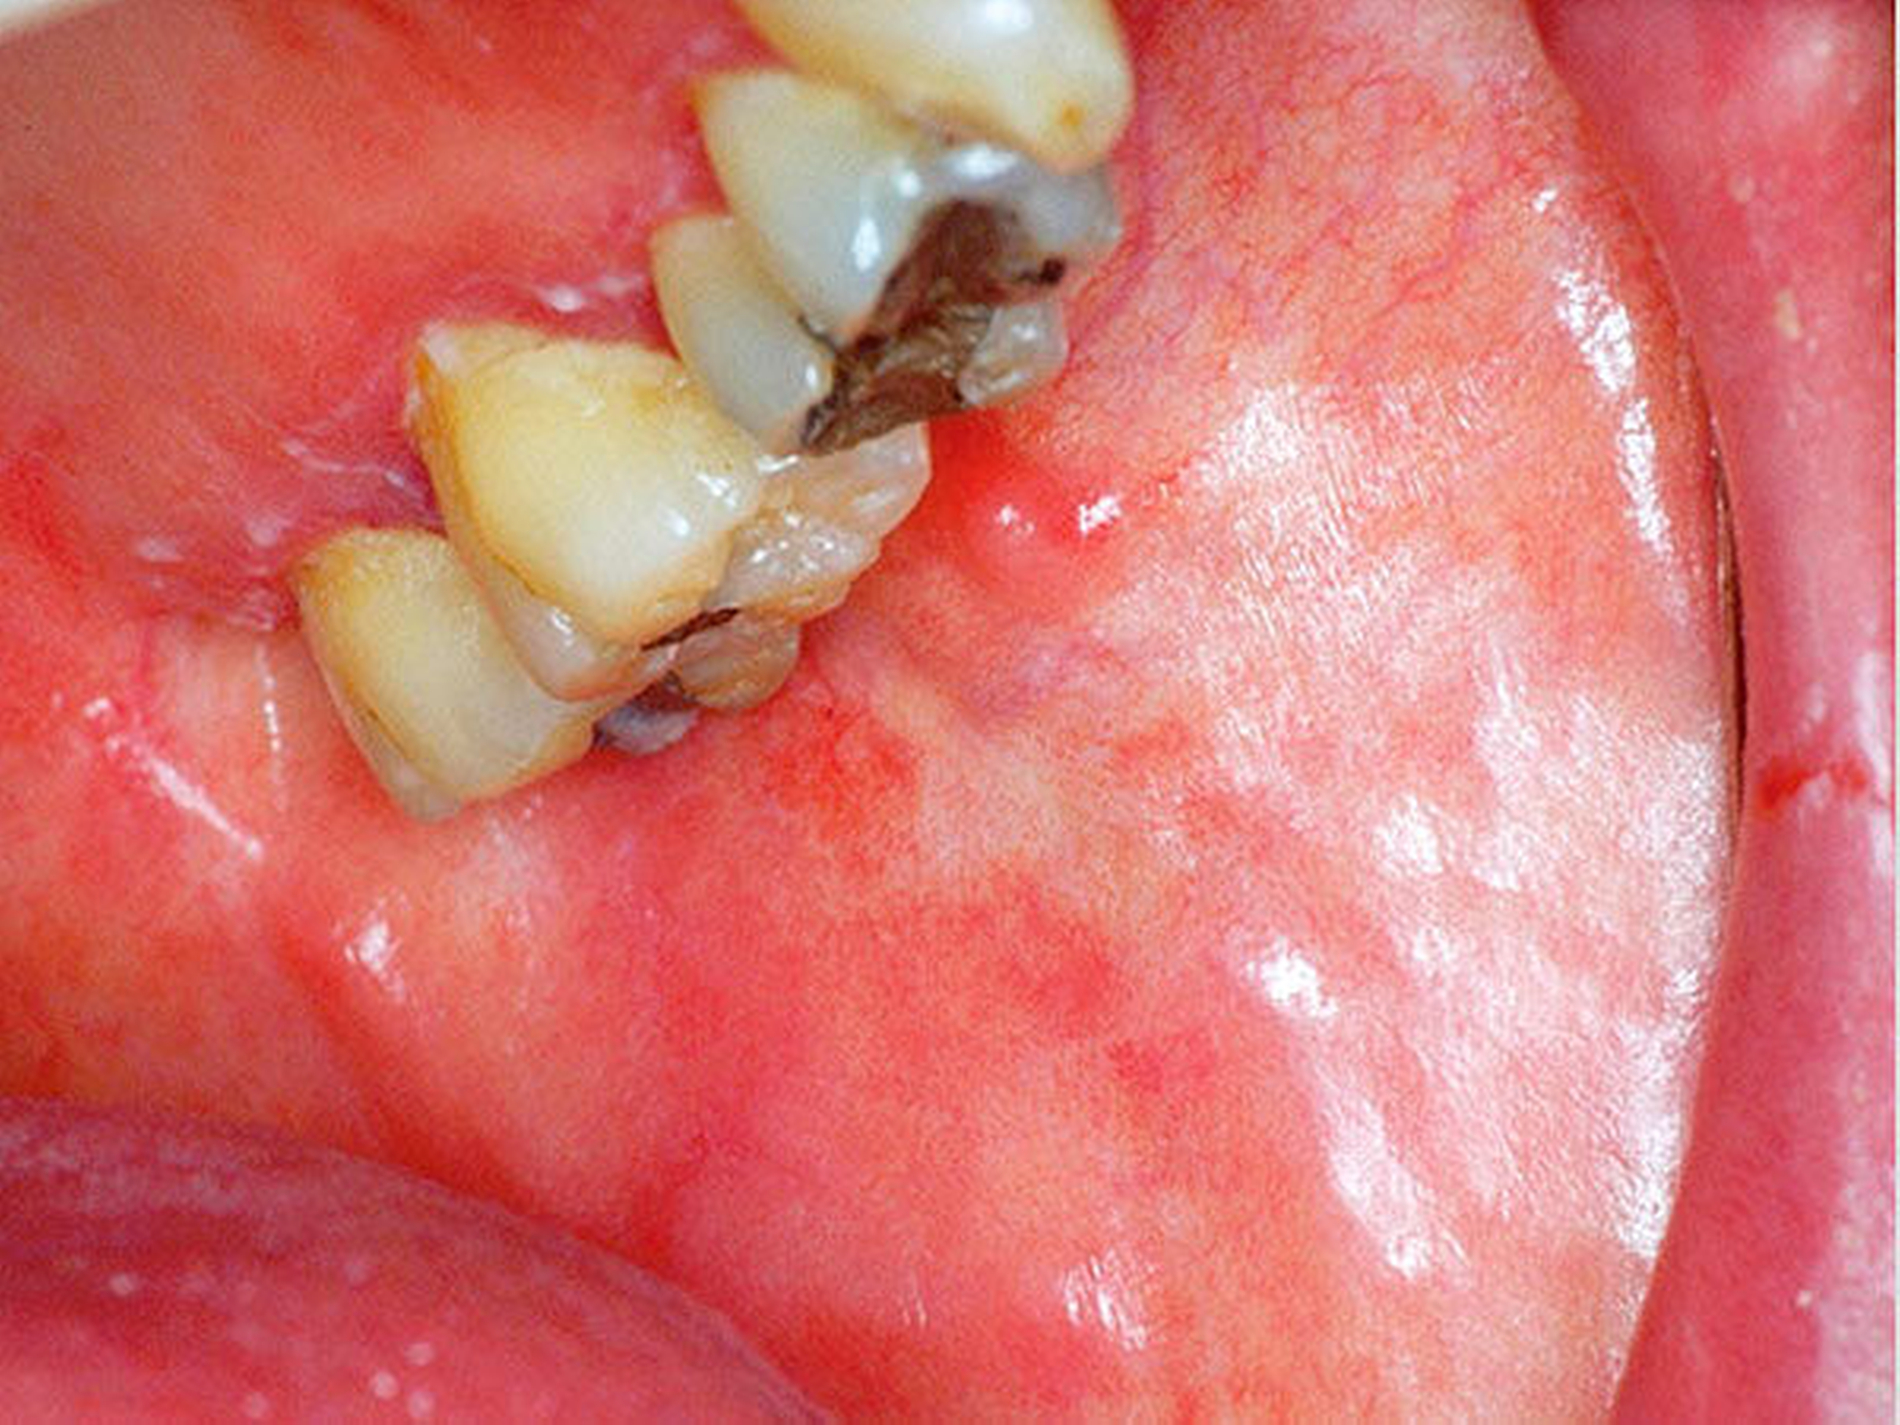

Das klinische Bild der oralen Mukositis ist vielschichtig und reicht von einfachen, lokalisierten Schleimhautirritationen bis hin zu schwersten Ulzera der gesamten oralen Mukosa [Bollig et al., 2016] (Abbildungen 4 und 5). In der Regel entwickeln sich die ersten Symptome innerhalb der ersten zwei Wochen nach Therapiebeginn. Das klinische Bild beinhaltet Irritationen, Erytheme, Inflammationen, Ulzera, Blutungen, Xerostomie und Geschmacksstörungen. Zusätzlich beklagen die Patienten starke Schmerzen und Parästhesien. Es kommt im Verlauf häufig zu Superinfektionen (Bakterien, Viren, Pilze), Kau- und Schluckbeschwerden, Einschränkungen in der Flüssigkeits- und Nahrungsaufnahme, Dehydrierung, Sprachproblemen, einer möglichen Behinderung der weiteren Tumortherapie und einer generellen Beeinträchtigung der Lebensqualität. Für das Gesundheitswesen entstehen außerdem hohe Kosten, unter anderem aufgrund der verlängerten Hospitalisierungszeit [Lalla et al., 2016; Panahi et al., 2016]. Der zeitliche Ablauf der beschriebenen klinischen Symptome und der Zeitpunkt ihres Auftretens können dabei variieren. Nach der WHO wird die orale Mukositis in fünf verschiedene Schweregrade (0 bis IV) eingeteilt [Bollig, 2016]:

Die Prävention und Therapie der oralen Mukositis ist komplex, wobei der Prävention insgesamt bei fehlenden kausalen Ansätzen der größte Stellenwert zugesprochen wird. In der Literatur werden über 40 Optionen zur Prävention und Therapie beschrieben, wobei viele nur in einer der fünf beschriebenen Phasen der oralen Mukositis wirken [Keiner, 2010]. Hinsichtlich der Prävention nehmen Zahnpflege, Optimierung der Mundhygiene, Schleimhautpflege und der engmaschige zahnärztliche Recall eine besondere Rolle ein. Neben den bekannten Maßnahmen, die im Zuge einer geplanten Bestrahlung im Kopf-Hals-Bereich durchzuführen sind, wie zum Beispiel der Fluoridierung mittels Fluoridierungsschiene zur Prophylaxe der Strahlenkaries als Folge der Xerostomie (Abbildung 6) und der Anfertigung eines Weichgeweberetraktors/Strahlenschutzschiene (3 bis 5 mm dicke PMMA-Folien) als Abstandhalter zwischen metallischen Restaurationen und den Schleimhäuten und somit zur Dosisreduktion der Strahlung an den Schleimhäuten, gilt besonders die prätherapeutische Zahnsanierung als eine der effizientesten Maßnahmen, die sowohl der Prophylaxe einer infizierten Osteoradionekrose (Abbildung 3) als auch einer oralen Mukositis (Abbildungen 4 und 5) zugute kommen. In diesem Zusammenhang sollten sowohl zur Prophylaxe der infizierten Osteoradionekrose als auch der Mukositis alle konservierenden und prothetischen Maßnahmen abgeschlossen, laufende Parodontalbehandlungen beendet und entzündlich beherdete oder nicht erhaltungswürdige Zähne vor Therapiebeginn entfernt sein. Sollten während einer laufenden Radio- und/oder Chemotherapie und einer möglicherweise auftretenden oralen Mukositis zahnärztliche und/oder zahnärztliche-chirurgische Behandlungen erforderlich sein, sollten diese nach Möglichkeit und kritischer Prüfung der Indikation in Anlehnung an die aktuelle S2k-Leitlinie zur Infizierten Osteoradionekrose nach Abschluss der Akuttoxizität, also etwa sechs bis acht Wochen nach Abschluss der Radio- und/oder Chemotherapie, durchgeführt werden [Krüger et al., 2018].